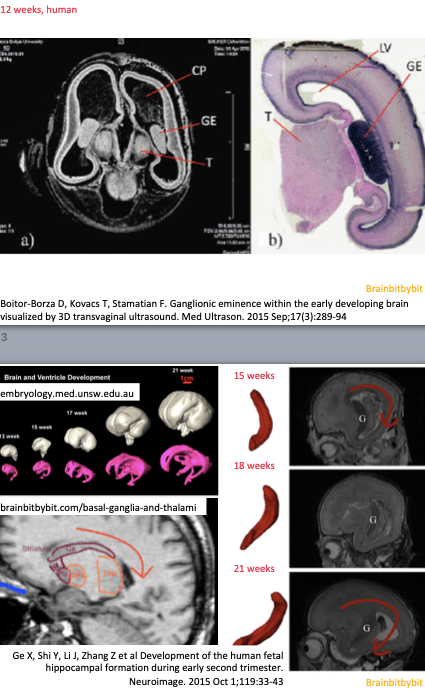

The caudate and putamen originate from the same structure which is named corpus striatum (in anticipation) and derived from the medial and lateral ganglionic eminences on the mesial, inner sides of the telencephalon. Between the 6th and 7th gestational week the telencephalon expands over the dorsal diencephalon/future thalamus, resulting in the C-shape of the caudate nuclei (and lateral ventricles). The ingrowing anterior limb of the internal capsule incompletely divides the corpus striatum into a medial caudate and lateral putamen and gives the striated appearance.

In the neocortex the GABAergic neurons originate from the ganglionic eminence and migrate tangentially mingling with the glutamatergic neurons from the ventricular zone. The main output neurotransmitter of the basal ganglia, which are derived of the ganglionic eminence, is also GABA. Acetylcholine is another abundant neurotransmitter in the basal ganglia, and thalami.